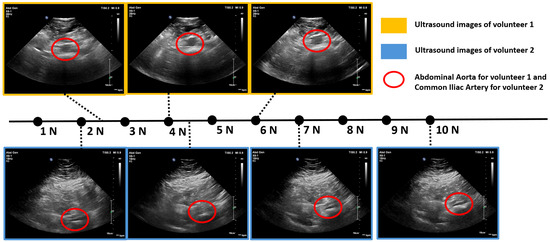

3.3.2. Volunteer Tests

The system successfully captured clear images of the abdominal aorta for both volunteers with different body shapes, which were reviewed by a registered clinical vascular scientist (HCPC CS20525) with 10 years of vascular ultrasound experience. Example images are presented in Figure 23.

Figure 23.

Abdominal aorta ultrasound images acquired by the robotic system: (a) Volunteer 1’s original image; (b) Volunteer 1’s images annotated by registered clinical vascular scientist; (c) Volunteer 2’s original image; (d) Volunteer 2’s images annotated by registered clinical vascular scientist.

Figure 24 illustrates the force readings and distributions recorded during automated ultrasound scans on two volunteers. The duration of each scan varies depending on the size of the selected region. The top graphs for both volunteers show a characteristic oscillatory pattern because of breathing motion, which was not observed in phantom tests. Regarding force distribution, Volunteer 1 demonstrated a lower proportion of forces within the desired range (39.6%) compared to Volunteer 2, where 65.1% of the forces fell within the target range. This difference can be explained by the higher BMI of Volunteer 2, where increased body fat and softer tissue facilitated smoother force control. The standard deviation of the forces further supports this observation, with Volunteer 1 exhibiting a higher standard deviation of 2.1 N compared to 1.6 N for Volunteer 2. The greater variability in Volunteer 1’s force readings is also attributed to the relatively firmer tissue, which made consistent force application more challenging. Nevertheless, the majority of force readings for both volunteers were within the ±2 N range, accounting for 93.1% and 96.7% of the forces for Volunteer 1 and Volunteer 2, respectively. The minor deviations outside this range primarily occurred at the beginning of the scan, as the robotic system transitioned from zero force to establishing surface contact. This is evident in the initial segments of the force value graphs. Throughout the scans, both volunteers reported no discomfort or pain.

Figure 24.

Force values and distributions in automated ultrasound image acquisition experiment on two volunteers. Red, green and blue colours in the middle and buttom graphs match with each other.